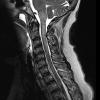

MYELIN (IMMUNE-MEDIATED)

Inflammatory Demyelination (19)